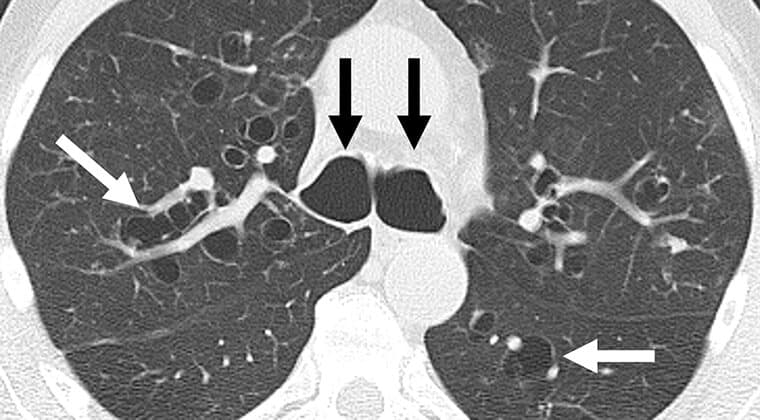

Cáncer de pulmón

Crecimiento anormal de células malignas en los pulmones, con alta tasa de mortalidad si no se detecta temprano.